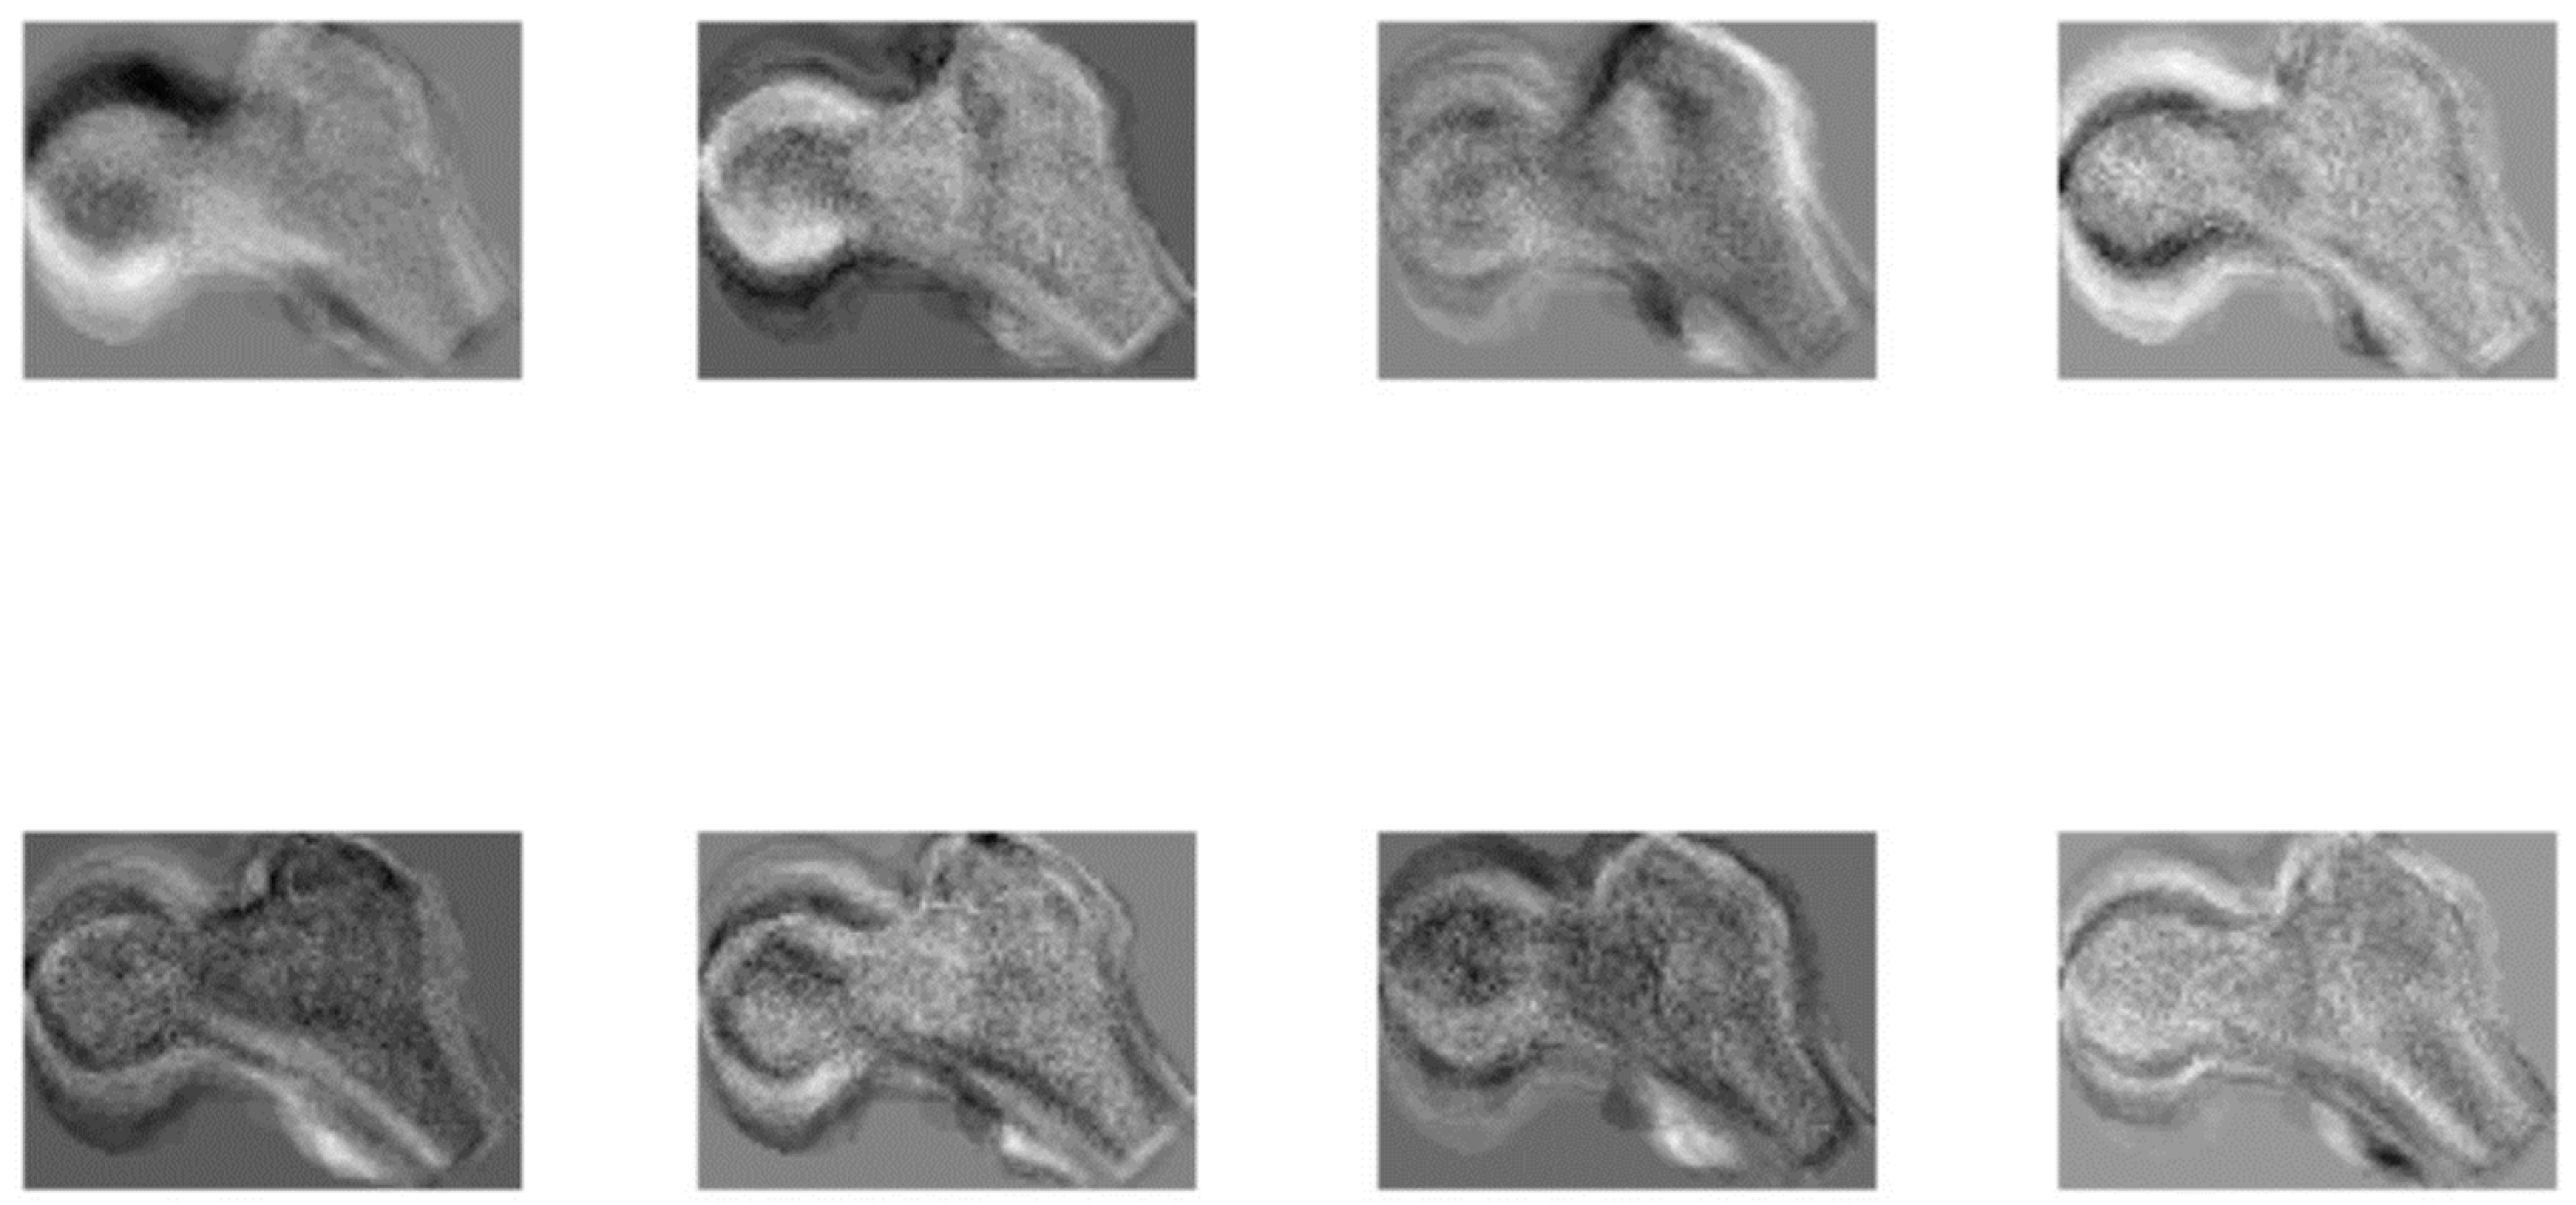

2.2.1. Acquisition and Segmentation

2.2.2. Age Estimation from the Femora Space with K-Nearest Neighbor Search